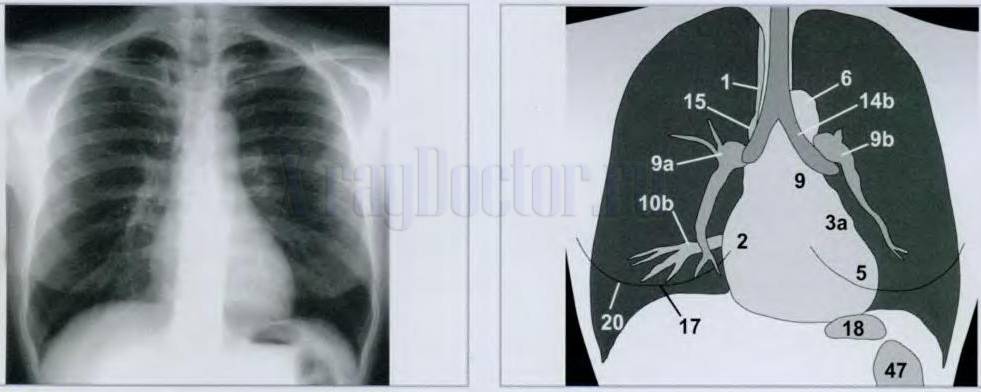

Снимок грудной клетки здорового ребенка: примеры и диагностика